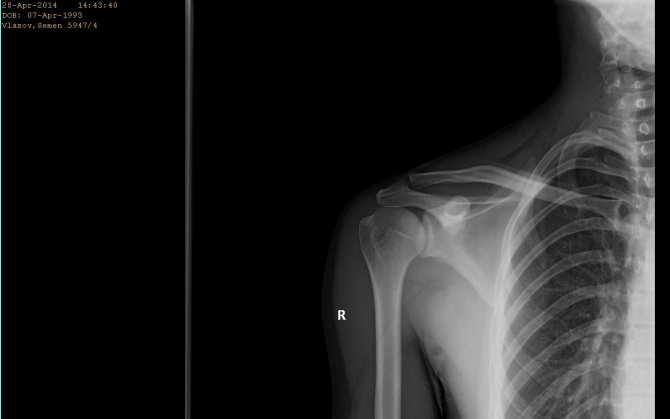

Стандартным инструментальным исследованием при подозрении на травму или заболевание плечевого сустава является рентген. Прибегают также к следующим методам диагностики:

Если специалист достаточно опытный, он сможет поставить предварительный диагноз, исходя из жалоб и результатов осмотра. Но точно определить, почему болят плечевые суставы и как лечить проблему получится только после рентгена. Также, исходя из конкретного случая, могут потребоваться другие обследования: